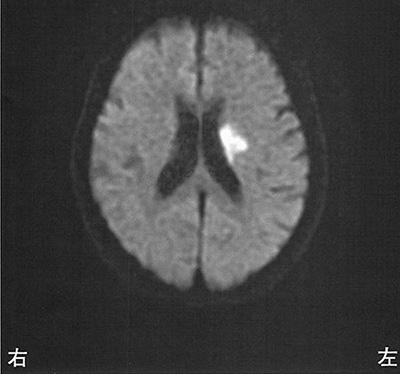

右内包後脚では、左上下肢の運動麻痺が見られるため、この選択肢は正しいです。